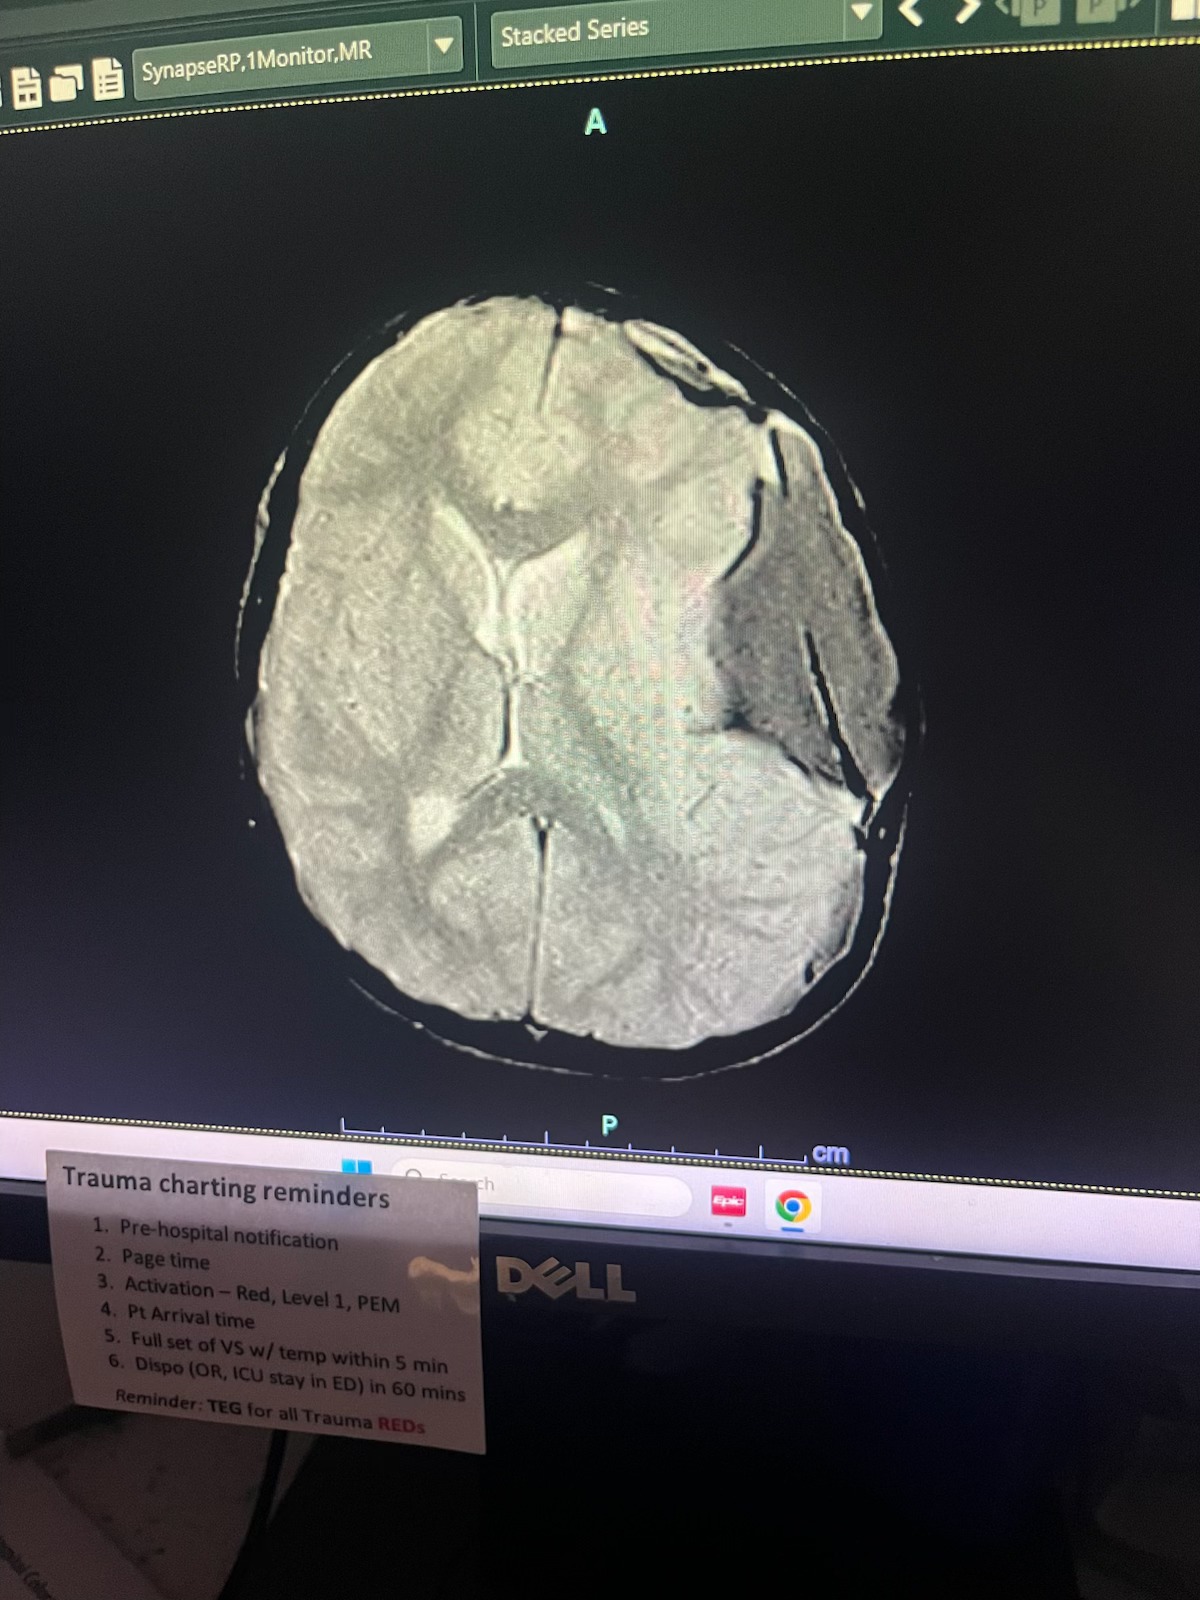

For the last year Kelly and Jeff's son, Finn, had been suffering from bad headaches. After going to his doctors for help, a scan revealed something life threatening. His doctors said what no parents expect to hear: "There's a helicopter waiting."

That helicopter ride, straight to Children's Hospital, saved Finn's life. Finn underwent emergency brain surgery and, miraculously, he's home and healing -slowly returning to school, Harry Potter and being a great big brother.